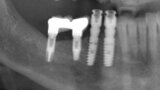

Figs. 9. Colocación de 2 implantes post-extracción en posiciones del 43 y 44 y control radiográfico post-extracción.

Figs. 10. Colocación de 2 implantes post-extracción en posiciones del 43 y 44 y control radiográfico post-extracción.